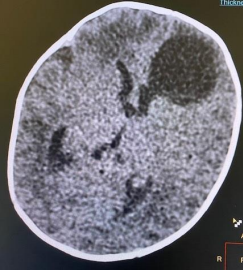

CT/MRI repeated (after completion the course of antibiotics) revealed no abscess but newly developed hydrocephalus.

Figure 4: MRI brain (post-operative craniotomy) in comparison with previous scans, there is complete resolution of the previously seen left frontal abscess collection with no residual or new collection, only mild post-operative gliosis, focal meningeal enhancement and haemosiderin rim seen.

There is  dilatation of the lateral and third ventricles maximum diameter 26 mm of the right lateral ventricle at atrium with more dilatation of the left frontal horn.